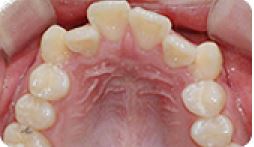

치아교정 설측브라켓 전후사례 | 2020.03.06 |